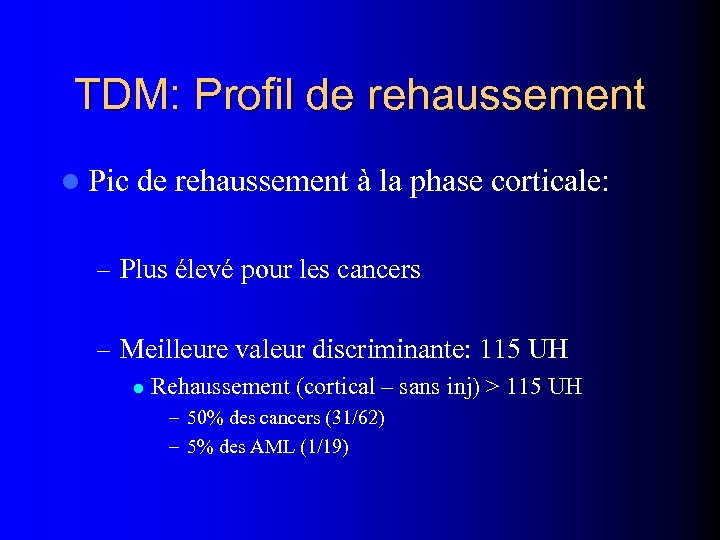

TDM: Profil de rehaussement l Pic de rehaussement à la phase corticale: – Plus élevé pour les cancers – Meilleure valeur discriminante: 115 UH l Rehaussement (cortical – sans inj) > 115 UH – 50% des cancers (31/62) – 5% des AML (1/19)

TDM: Profil de rehaussement l Pic de rehaussement à la phase corticale: – Plus élevé pour les cancers – Meilleure valeur discriminante: 115 UH l Rehaussement (cortical – sans inj) > 115 UH – 50% des cancers (31/62) – 5% des AML (1/19)